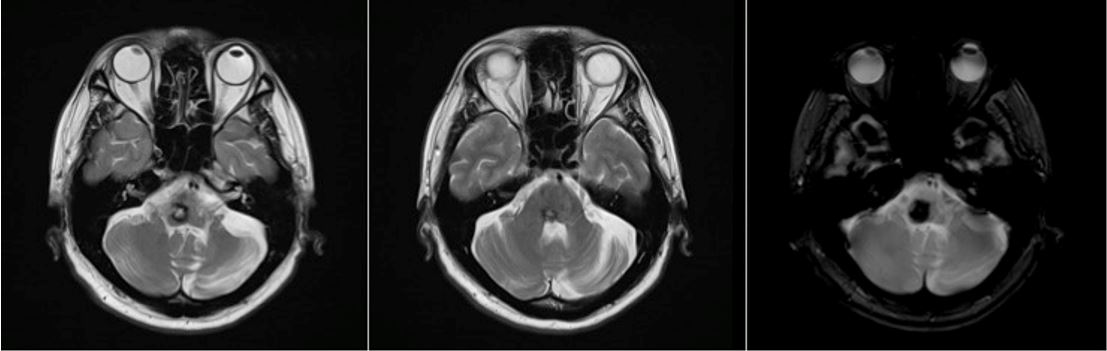

On magnetic resonance imaging, there is a hemorrhage with a complete hemosiderin ring at the level of the pons/ponto-medullary junction, associated with a well-defined lesion with a “popcorn ball” appearance resembling that of a cavernoma (Figure 3 [Fig. 3], Figure 4 [Fig. 4], and Figure 5 [Fig. 5]).

Figure 3: T2-weighted images from the patient’s cranial magnetic resonance imaging

Figure 4: T1-weighted images from the patient’s cranial magnetic resonance imaging

Figure 5: Time of flight image from the patient’s cranial magnetic resonance angiogram

Cavernomas are angiographically occult lesions, which is why conventional T1- and T2-weighted magnetic resonance imaging (MRI) is still being used for its diagnosis [12]. The MRI is able to accurately detect cavernomas, which have a pathognomonic “popcorn-ball” appearance due to loculated hemorrhages, hemosiderin deposition around the primary lesion, and gliotic reaction [12]. Based on imaging, differentials may include hemorrhagic brain metastasis, gliomas, and hemorrhagic telangiectasias (Osler-Weber-Rendu disease) [12].